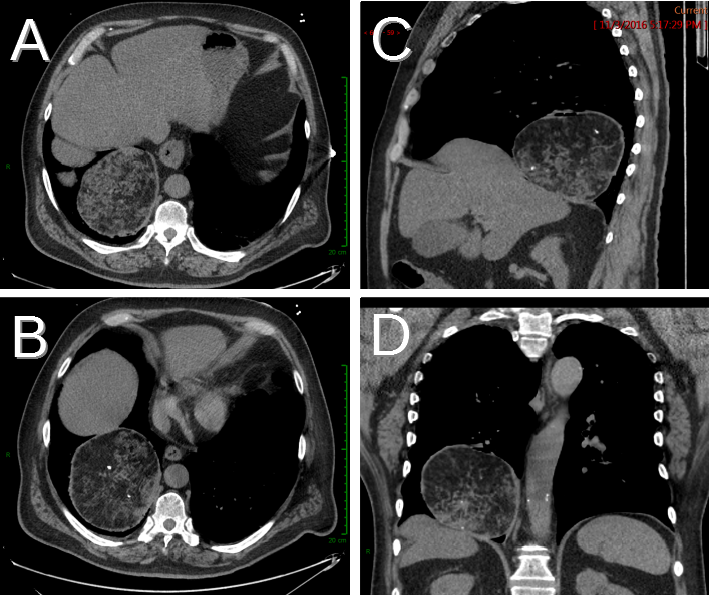

Chondromesenchymal Hamartomas In A 24 Year Old Male Mimicking A Posterior Mediastinal Tumor And A 5 Month Old Boy With Postoperative Disseminated Intravascular Coagulation Two Case Reports Diagnostic Pathology Full Text

Chondromesenchymal Hamartomas In A 24 Year Old Male Mimicking A Posterior Mediastinal Tumor And A 5 Month Old Boy With Postoperative Disseminated Intravascular Coagulation Two Case Reports Diagnostic Pathology Full Text from media.springernature.com

A large hamartoma of the spleen. A rare cause of bronchial occlusion. Hamartoma, benign tumourlike growth made up of normal mature cells in abnormal number or distribution. A hamartoma (from greek hamartion bodily defect) is a benign (noncancerous) tumorlike malformation made up of an abnormal mixture of cells and tissues found in areas of the body where growth occurs. A hamartoma is a focal malformation that resembles a neoplasm in the tissue of its origin. This is not a malignant tumor, and it grows hamartomas, while generally benign, can cause problems due to their location. This zone shows sheets of immature cells with bland, ovoid vesicular nuclei. It is considered a developmental error and can occur at a number of sites. A mass resembling a tumor that represents anomalous development of tissue natural to a part or organ rather than a true tumor. Breast hamartomas are responsible for roughly 5 percent of benign breast masses. A large hamartoma of the spleen. Hamartomas can be difficult to distinguish from cancers but do have some characteristics that set them apart. Residents and fellows contest rules | international ophthalmologists contest rules.

The growth is about 9 cm a hamartoma is a mostly benign,2 local malformation of cells that resembles a neoplasm of local tissue but is usually due to an overgrowth of.